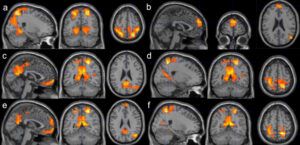

The past two decades have brought us unprecedented insights into meditation’s effects on the anxious brain. Using advanced neuroimaging techniques like fMRI and MRI, researchers have mapped exactly how meditation creates lasting changes in brain structure and function. What they’ve discovered is revolutionary: meditation doesn’t just help you feel better temporarily—it literally rebuilds your brain for resilience, calm, and emotional regulation.

A groundbreaking study led by Sara Lazar at Harvard’s Massachusetts General Hospital found that eight weeks of mindfulness meditation training produced measurable changes in brain regions associated with memory, sense of self, empathy, and stress. Most remarkably, participant-reported reductions in stress were correlated with decreased gray-matter density in the amygdala, which is known to play an important role in anxiety and stress.

Further research published in Frontiers in Human Neuroscience showed that the amygdala response to emotional stimuli is lower when the subject is in a meditative state of mindful-attention.